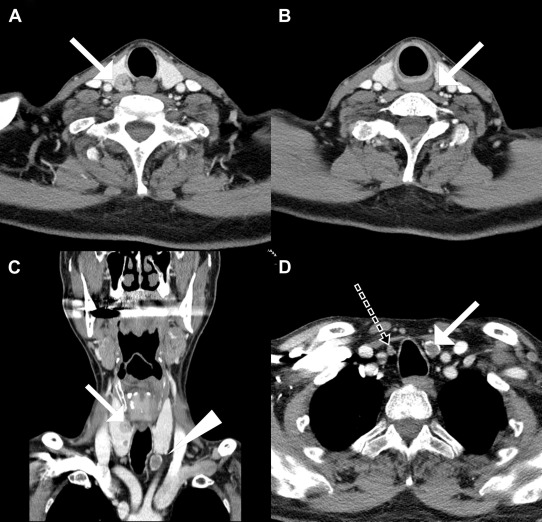

To treat symptomatic tertiary hyperparathyroidism with osteoporosis, the patient was referred to endocrine surgeon. The mean T-score of the lumbar spine (L1–L4), measured by dual-energy X-ray absorptiometry, was –3.1. Computed tomography of the neck showed three enlarged parathyroid glands (Fig. 2). Fig. 3 represents a 2-hour delayed 99mTc-sestamibi scintigraphy (MIBI scan) showing an increased uptake in the right inferior parathyroid gland. During the neck exploration, four enlarged, soft, oval, and yellowish parathyroid glands were observed (right superior: 1.8 × 1.5 cm2; right inferior: 1 × 1 cm2; left superior: 1 × 0.7 cm2; left inferior: 2.5 × 1.8 cm2). Frozen biopsy performed intraoperatively on the left superior parathyroid revealed parathyroid hyperplasia. Left superior parathyroid gland was preserved partially, while other lesions were removed completely.

Enlarged parathyroid glands in computed tomography. (A) Right superior ...

Figure 2.

Enlarged parathyroid glands in computed tomography. (A) Right superior parathyroid (arrow); (B) left superior parathyroid (arrow); (C) right superior parathyroid (arrow) and left inferior parathyroid (arrowhead); and (D) left inferior parathyroid (white arrow) and right inferior parathyroid (dotted arrow). Right inferior parathyroid was mistakenly identified as a lymph node on initial computed tomography. Intraoperative findings confirmed it to be a right inferior parathyroid.